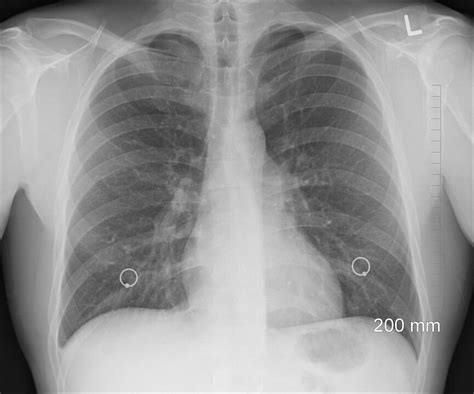

- RTG hrudníka: Röntgenový snímok hrudníka je bežným a účinným nástrojom na vizualizáciu pľúc. Na snímke sú viditeľné zápalové zmeny, ako sú infiltráty alebo zhrubnutie pľúcneho tkaniva, ktoré pomáhajú určiť lokalizáciu a rozsah postihnutia. V niektorých prípadoch môže byť potrebné aj CT vyšetrenie hrudníka pre detailnejší obraz.